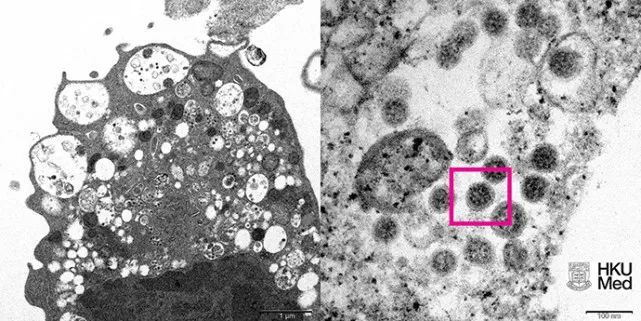

研究人员需要更多的时间,来全面了解奥密克戎变异株。并了解其传播能力和严重程度,以及疫苗对其的效力。12月8日上午,香港大学医学院发布了奥密克戎变异株的电镜照片。此前,港大微生物学系已经从临床标本中成功分离出奥密克戎变异株,并且和内地疫苗生产商共享了分离成果。

(图左)低倍电子显微镜下感染新型冠状病毒奥密克戎变异株后的猴肾细胞(Vero E6)。照片显示细胞受损,肿胀囊泡,囊泡内含有黑色小病毒颗粒。

(图右)高倍电子显微镜下受感染的Vero E6细胞。照片显示病毒颗粒表面呈现皇冠形的刺突蛋白(见红框)。